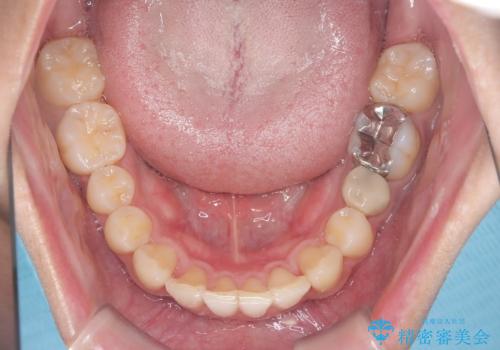

前歯のガタガタを治したい。

- 凸凹を治したいと来院された患者様です。

インビザラインにて、遠心移動を行いながら綺麗に配列することができました。